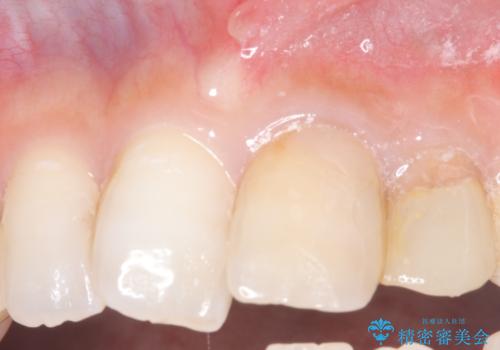

- 主訴:上の前歯の根元部分が欠けた、欠けた歯たまに揺れている気がする。

過去にも同じように欠けて、通っている歯科医院で応急処置してもらったが、また欠けてしまった。

左上2番の唇側歯頚部が欠けており、根管治療を受けている歯でした。

レントゲン写真撮影を行ったところ、歯の中の土台が外れ欠けている状態でしたので土台と被せものの治療を行うこととしました。